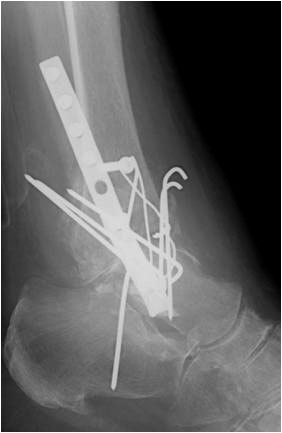

• Primäre oder posttraumatische Arthrose des OSG und USG (Abbildung 1, Abbildung 2).

• Revision einer gescheiterten Fusion des OSG/ USG (Abbildung 3, Abbildung 4).

• Pseudarthrosen (Abbildung 5, Abbildung 6).